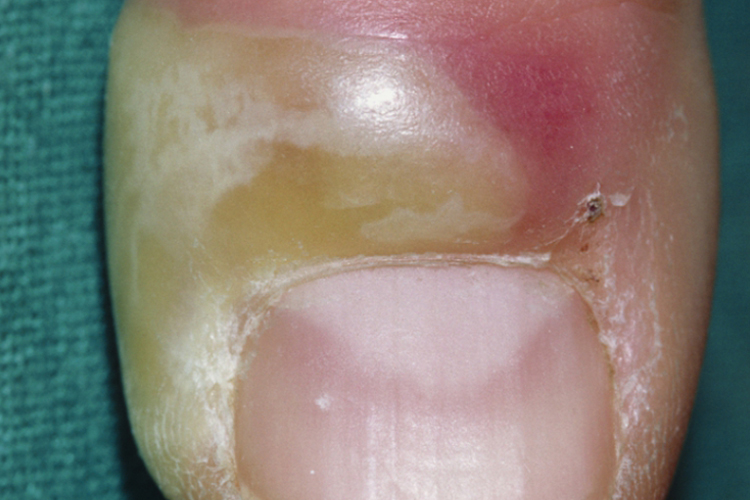

慢性甲沟炎表现为皮肤红、肿、痛,但程度通常轻于急性甲沟炎。患者的临床症状也可呈现突然间加重,出现化脓现象,还会出现甲周近端皮肤褶皱抬起,并和下方的甲板分离。甲形态的变化,如隆起、沟槽、褪色、甲板变圆等。